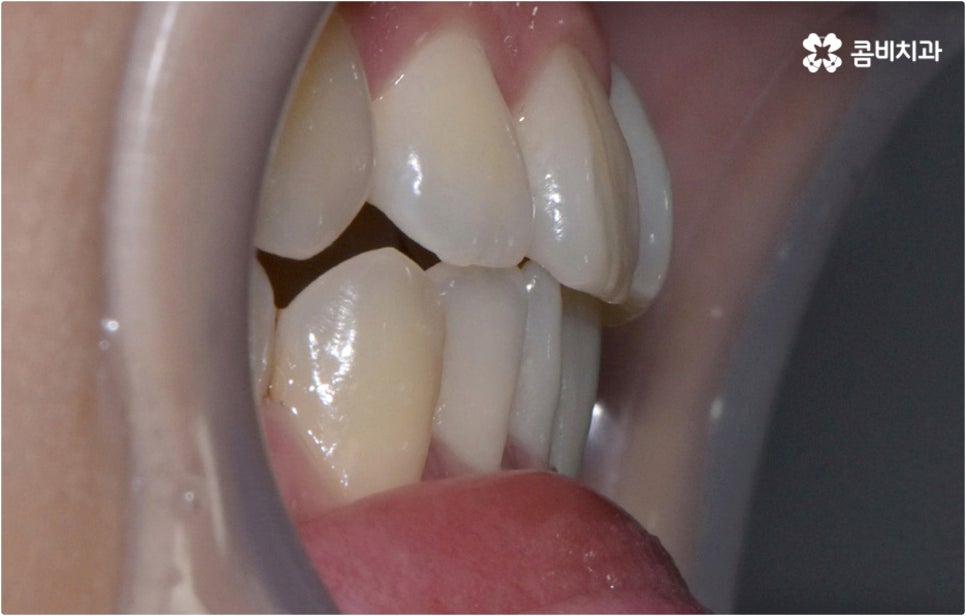

예를 들어 클리피씨교정 장치를 이용하면 기간적인 부분과 심미적인 부분의 부담을 함께 줄일 수 있어요. 예전처럼 미세 철사나 고무줄을 이용하여 와이어를 고정시키는 것이 아니라 자가결찰방식을 이용하기 때문에 클리피씨교정 장치를 사용하면 마찰로 손실되는 교정력이 줄어 보다 부드럽고 지속적인 치아 이동이 가능하게 되며, 치아 색상과 비슷한 세라믹 재질의 브라켓을 부착하기 때문에 말을 하거나 음식을 먹는 등 자연스럽게 입을 벌리는 상황에서 장치가 크게 눈에 띄지 않아 심미성 또한 우수하다고 할 수 있습니다. 이러한 장점으로 요즘 가장 많이 쓰이고 있는 장치는 역시 클리피씨 인데요, 이때 만약 환자분께서 아예 브라켓이 보이지 않는 것을 원한다고 한다면 치아설측교정 장치를 고려해 볼 수 있어요.

치아설측교정 은 겉으로 장치가 드러나지 않아서 가까운 사람이 아니면 교정 치료를 진행한다는 것을 알아차리기 힘들 정도로 심미성이 뛰어난데, 이러한 장점을 가지고 있는 반면 혀가 아랫니 쪽 장치에 닿다 보니 발음이 불분명해지거나 이물감 및 통증을 느끼는 경우가 있어 주의할 필요가 있어요.

이런 때는 치아설측교정 대신 비교적 잘 보이는 윗니는 설측으로 진행하고, 입술에 가려 잘 보이지 않는 아랫니는 순측(입술쪽)으로 진행하는 콤비교정을 이용하면 발음, 이물감, 통증 문제를 해결할 수 있습니다. 콤비교정 시 치아 겉면에 부착하는 아랫니 브라켓의 경우 치아와 색상이 비슷한 세라믹 재질을 이용하기 때문에 심미성도 크게 떨어지지 않으며 치아설측교정 으로 전체를 진행하는 것 보다 비용적인 부담도 줄여주므로 설측 교정 치료를 생각하시는 분들이라면 콤비교정 역시 함께 알아보시길 권유드리고 있어요.